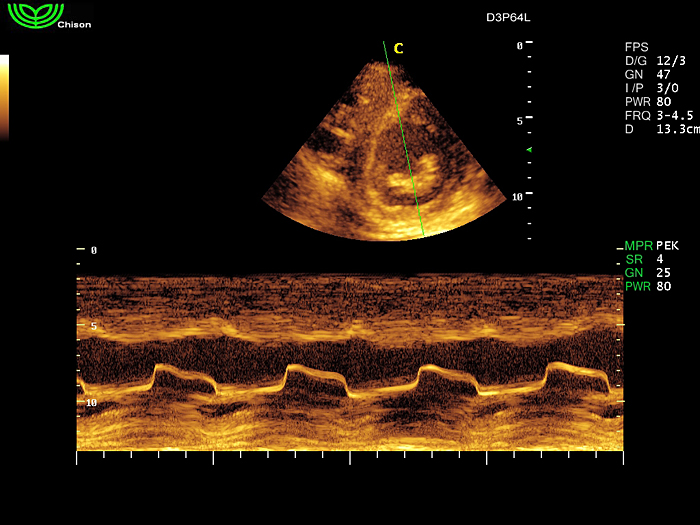

D3P64L 3.0МГц, фазированная решетка.

2.0МГц – 4.4МГц. Применения: кардиология, брюшная полость, акушерство. |